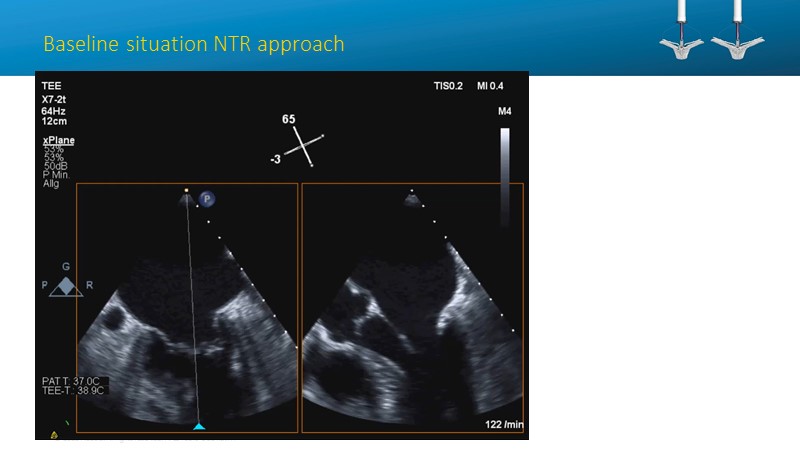

- To learn how will product innovation (Mitraclip NTR / XTR) drive improvement in procedural and clinical outcomes (EXPAND)